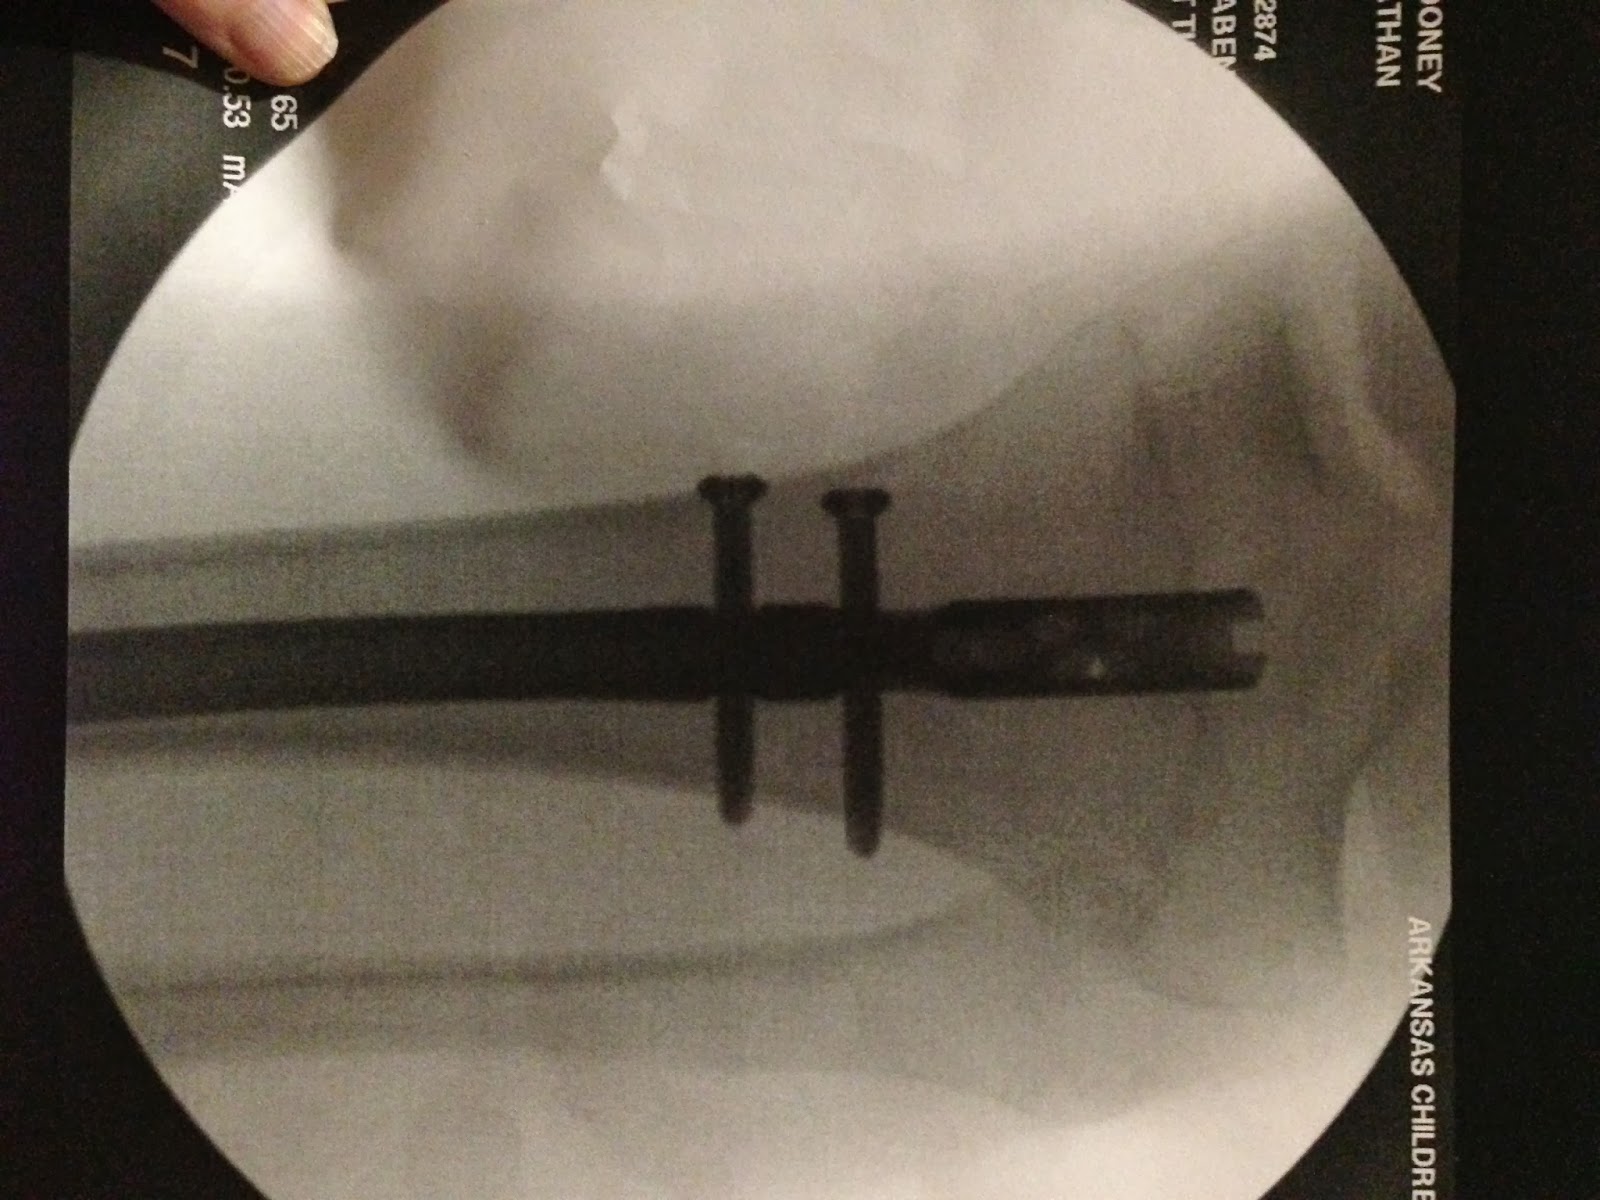

I was allowed to go with Nate to the pre-op room. He seemed a little nervous, but it didn't take long for the "happy juice" to kick in and he wouldn't have cared if the walls fell down around him. My parents, my sister, my mother-in-law and sister-in-law came and sat with me in the waiting room. They explained that they would let us know when the surgery began, and a nurse would call every hour with an update. Hour one, of course, was when I had chosen to go get something to eat. The nurse spoke with my sister-in-law, and she said everything was going fine. Hour two came and went, with no update. Hour three. No update. Finally, after 4 1/2 hours of surgery, the doctor came out to visit with us. He said Nate had made it fine, the surgery went well, and it was definitely Compartment Syndrome. He said Nate had long incisions down each side of his calf that would be left open and attached to a wound vac until the muscles healed. He also said he placed a rod in his calf through an incision in his knee, and there would be scars on his outer ankle and outer knee where the screws were. He showed us the x-rays…